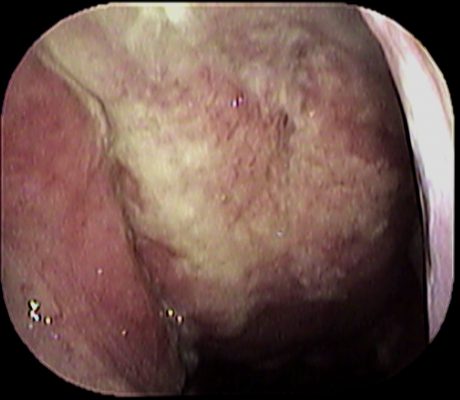

当院は耳鼻科なので、ノドもしっかりチェックします↓

インフルエンザは陰性でした。

ここで「 オヤッ

」と気付くわけですが

どこに異常があるか分かりますでしょうか?

正解は、ここです↓

赤丸部分が赤くなり 膿が付着しています。

病名は「咽頭側索炎」です。

この場合、さらに追加でチェックすべき場所があるのでファイバーを使用します。

どこをチェックするかと言いますと↓

上咽頭です。

こんな感じでファイバーを挿入したところ↓

上咽頭にも炎症があり、膿が大量に付着していました。

「急性上咽頭炎」の状態です。

病名は、「咽頭側索炎」と「急性上咽頭炎」です。

これが高熱🤒と咽頭痛😫の原因でした。

ノドをしっかり診察することは大切ですね